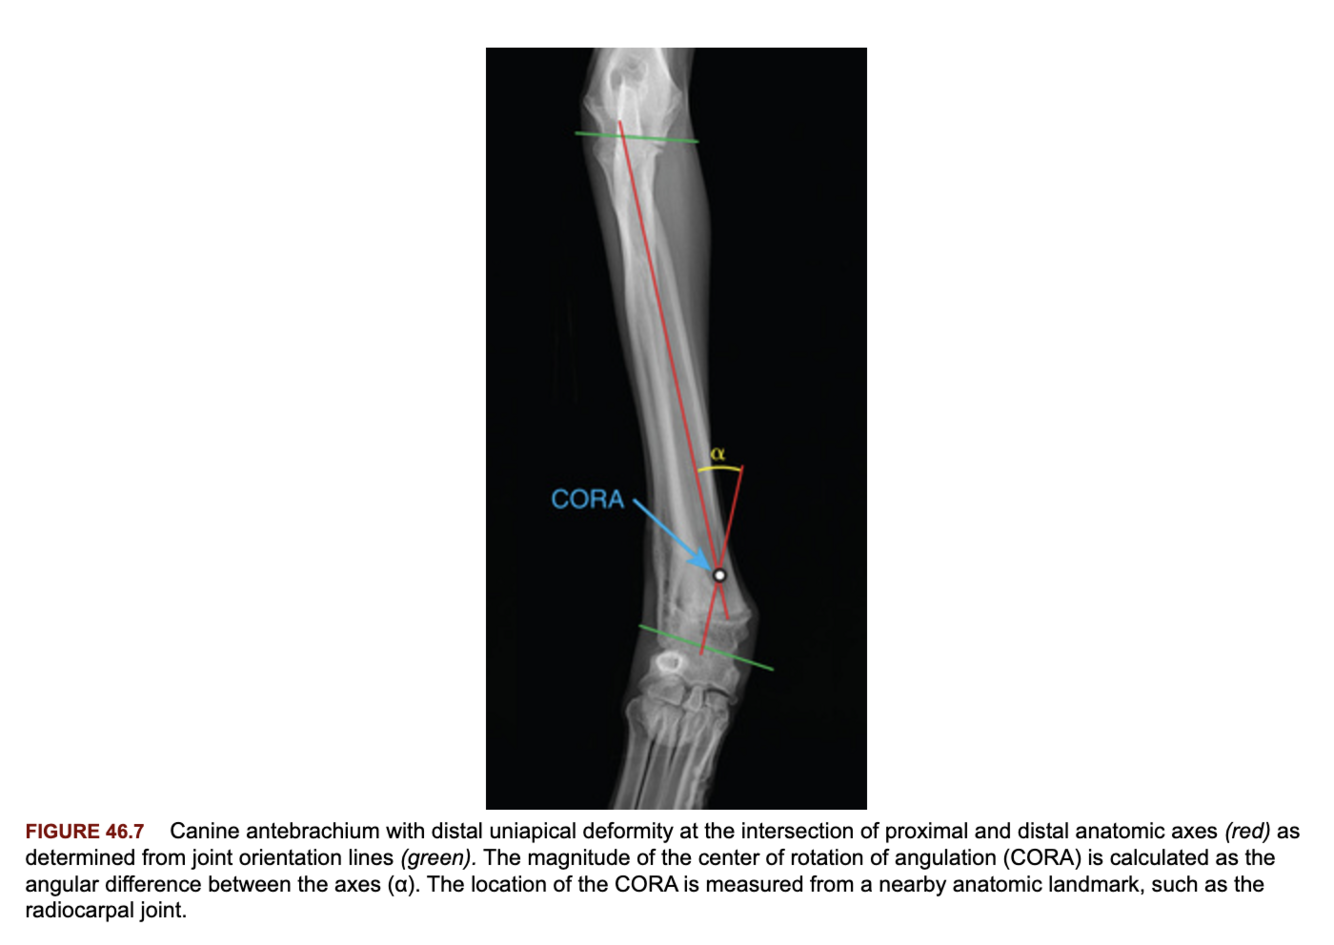

What is a CORA?

A

The center of rotation of angulation and is essentially the apex of an angular limb deformity.

Has a location, plane and magnitude.

Q

How is a CORA measured?

The intersection of the axes of the bone as drawn through the joint orientation lines. The angle of the axes is based off the contralateral limb or library of reference values.